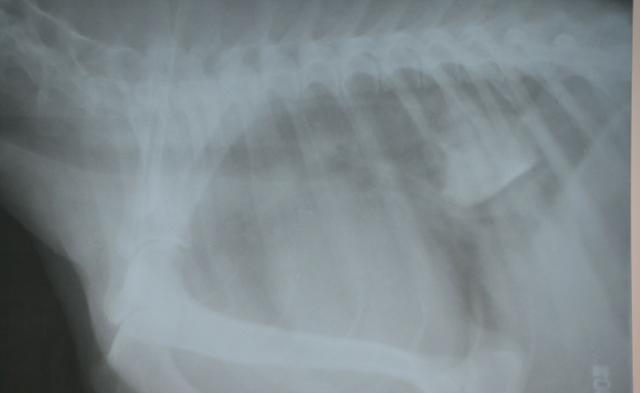

化验:X光片显示狗狗的食管末端,有一块骨头卡在上面,骨头还算比较规则。

治疗:灌服石蜡油和利多卡因,比较幸运的是这块骨头的位置特别靠近贲门,所以成功的用润滑剂,让骨头进入到了胃里面。

3天后再次拍X光,骨头完全消化,排出体内了。

颈部和胸部的X光2张,这是诊断食道异物最重要的检查方式(正位和侧位各一张)食道钡餐X光造影,可以更清楚的观察异物的形状以及对食管的损伤程度,对手术方式起到评估作用。(可以和内窥镜选择使用一种)内窥镜可以确诊异物的具体位置,而且可以直观的看到异物以及食道的损伤情况。血常规和生化检查,对炎性反应和狗狗的机体做评估,选择手术方案和时间。